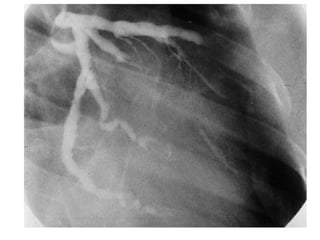

Markis JE. Am J Cardiol 1976;37(2):217

Ectasia Markis JE.Am J Cardiol 1976;37(2):217